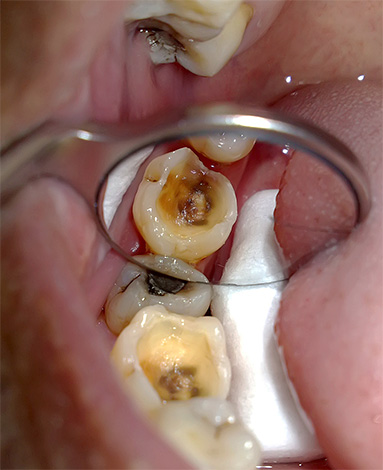

Nella fotografia sotto, i canali radicolari sono chiaramente visibili: ognuno di essi deve essere accuratamente pulito dai resti della polpa, altrimenti l'infezione conservata in essi può portare a gravi conseguenze in futuro: